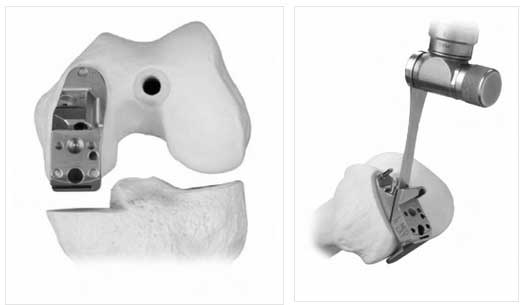

PATELLOFEMORAL

- PATELLA REPLACED WITH POLYTHYLENE INSERT

- TROCHLEA WITH UNCONSTRAINED METAL

- INLAY AND ONLAY TECHNIQUE: INLAY MY PREFERRED- LAZY

- PATELLAR TRACKING TO BE CLOSELY EXAMINED BEFORE SURGERY, MOST REQUIRE LATERAL RELEASE.

UNICOMPARTMENTAL

- MEDIAL MOST COMMON

- OPTION OF ALL POLY OR METAL BACKED

- ACL SHOULD BE INTACT

- FUNCTIONAL ACL SEEN BY AN ANTERO MEDIAL WEAR PATTERN, IF THE WEAR IS ON POSTERIOR ASPECT- POOR CANDIDATE

- 1-2MM THICKNESS BONE TO BE CUT FROM TIBIA AND 7MM FROM FEMUR